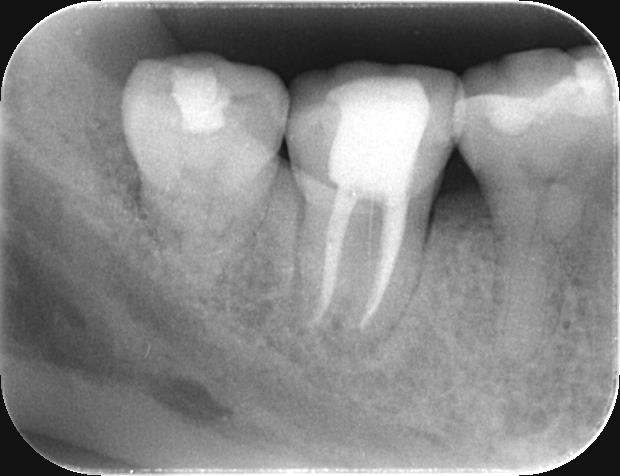

実際の症例

-

治療前

治療後

| 治療内容 | 精密根管治療 | 期間 | 3~6ヶ月※状態に応じて変わります |

|---|---|---|---|

| 治療回数 | 5回 | 費用 | 再根管治療170,000円(税込 187,000円) |

| リスク 副作用 |

歯質の状況に応じて抜歯の診断。もしくは歯根端切除に移行あり。 | ||